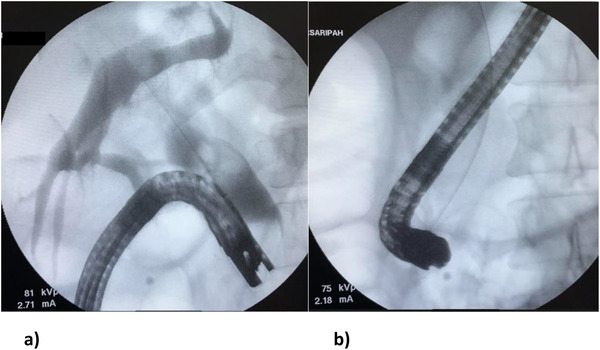

A 42‐year‐old female with no prior medical illness presented with fever, epigastric pain, and vomiting of 3 days’ duration. On assessment in the Emergency Department, she appeared septic with a blood pressure of 70 of 46 mm Hg and a pulse of 98/min. Temperature was 37.5°C. Further examination revealed that she was icteric. She had crackles on both lung bases with the apex beat appreciated at the right 5th intercostal space. Blood parameters were notable for deranged Liver Function Test with total bilirubin, 5.4 mg/dL; aspartate aminotransferase (AST), 481 U/L; and alanine aminotransferase (ALT), 333 U/L. The Blood Film for Malaria Parasite which was positive for Plasmodium Falciparum added to the complexity of the case. Radiographic imaging of the chest was consistent with situs inversus. She was initiated on antibiotics, antimalarials, and vasopressors. CT imaging revealed choledocholithiasis with upstream dilatation of the biliary tree (Figure 1). There were no associated anatomical abnormalities of the CBD. The size of the CBD stone (2.2 × 1.8 cm) depicted on the CT had raised concerns on the amenability of an endoscopic intervention in achieving stone clearance. However, during the multidisciplinary meeting, a decision was reached to proceed with ERCP and biliary decompression as a temporizing measure in view of the anticipated delay in surgery due to ongoing COVID‐19 pandemic. Patient was placed in supine position with the endoscopist on the left side. The supine position was preferred by the anaesthetist for better control of the airway in the event of a desaturation episode. Following administration of sedation with propofol (100 mg), ERCP was performed with a side‐viewing endoscope (TJF‐Q180V J; Olympus, Tokyo, Japan). The endoscope was advanced into the duodenum and was rotated 180° clockwise with some degree of torsion. The papillary orifice was noted in the 2 o’clock direction, with the scope in long position. Owing to the location of the papilla, a rotatable sphincterotome (Leo Med triple lumen sphincterotome RST0725N, Leo Medical Co., Ltd, Changzhou City, Jiangsu Province, China) (Figure 2a) was employed to achieve deep biliary cannulation. Cholangiogram revealed a large mid CBD stone following which, a wire‐led sphincterotomy was performed (Figure 2b). Fluoroscopy image was mirrored to make cholangiogram interpretation more familiar. We then advanced a stone extraction catheter (Leo Med stone extraction catheter QS‐2A00, Leo Medical Co., Ltd, Changzhou City, Jiangsu Province, China) into the CBD and after inflating it we used the balloon as an anchor to perform the shortening manoeuvre of the duodenoscope (Figure 3a). This was essential as we had anticipated technical difficulty in extracting the stone owing to the axis between the 2 o’clock position of the ampulla and the duodenoscope. This manoeuvre was done by maintaining traction on the duodenoscope while performing a 180˚ clockwise torque. With this technique, we attained a short position of the endoscope (Figure 3b) and restored the papilla to the conventional 11 o’clock position (Figure 4). Nevertheless, attempts for CBD stone removal using an extractor balloon catheter failed in view of the size of the stone as well as the angulation of the duodenoscope. We proceeded with stenting using a straight plastic stent to decompress the biliary system. The procedure took approximately 35 min, and there were no episodes of desaturation throughout the procedure. Our patient had a favorable recovery following the procedure, with improvement of both clinical and biochemical parameters. She underwent Common Bile Duct Exploration (CBDE) and cholecystectomy 2 weeks following the ERCP procedure and was discharged well.